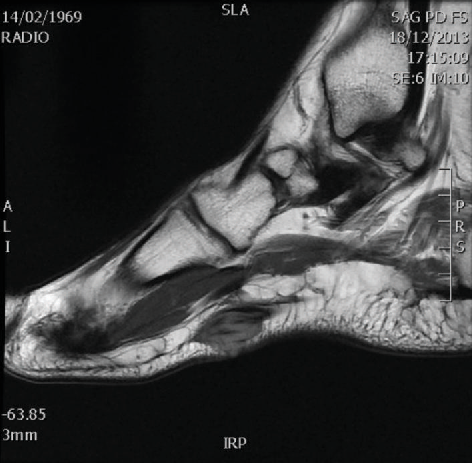

초음파 검사나 MRI 검사로

확인 가능하고,

X-ray에서는 확인하기 어려워

족저근막염으로 오해하기 쉽습니다.